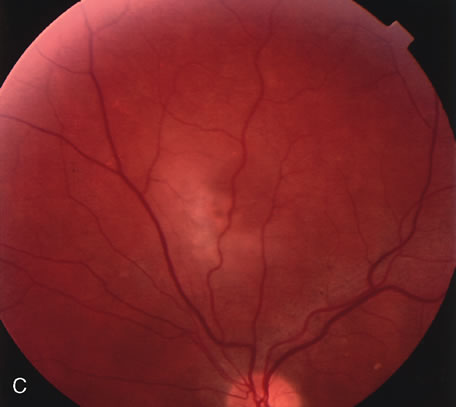

Clinically discernible peripheral dependent bullous neurosensory detachments have been described in patients with chronic CSC.85–92 Yannuzzi and co-workers first characterized the presence of RPE atrophic tracts extending inferiorly in the fundus periphery secondary to antecedent retinal detachment in patients with CSC.85 Presumably, there is a particularly severe and/or longstanding leakage of fluid from an RPE defect in the subretinal space at the posterior pole. The subretinal fluid gravitates inferiorly to form a dependent neurosensory detachment in a “flask,” “teardrop,” “dumbbell,” or “hourglass” pattern (Fig. 31). Sometimes the tract of subretinal fluid connecting the macular detachment with the bullous neurosensory detachment in the inferior hemisphere is so shallow that it is very difficult to appreciate. The RPE under the chronic retinal detachment experiences atrophic changes that appear as atrophic RPE tracts connecting the posterior pole with the dependent retinal detachment. The retina itself develops secondary manifestations including pigment migration, capillary dilatation (telangiectasia) proximally and capillary nonperfusion (ischemia) distally to the area of detached retina (see Fig. 31). The changes in the RPE consist of both RPE atrophy and pigment clumping in the form of perivascular deposits or bone spicules, a condition described by Gass as a “pseudoretinitis pigmentosa–like atypical CSC presentation.”87

Fig. 31. A 47-year-old woman with an18-year history of central serous chorioretinopathy in both eyes. A. Color photograph composite of the left eye shows bullous dependant detachment of the neurosensory retina inferiorly. B. Fluorescein angiogram composite reveals diffuse decompensation of the retinal pigment epithelium, multiple scattered pigment epithelium detachments 9PEDs), and obliteration of the retinal capillaries in the region of the detachments. Note the presence of early neovascularization at the junction between perfused and non-perfused retina. C. Clinical photograph of the left eye shows PED superior to the optic disc partially surrounded by fibrin deposits. D. Fluorescein angiography confirms the presence of active leakage from the serous PED. E, Color photograph composite of the same eye 2 months after laser treatment of the site of leakage reveals partial resolution of the detachment and lipid precipitation. F. Clinical photograph composite 16 months after the laser treatment in the area of the leakage shows complete resolution of the detachment and partial reperfusion of the inferior retina.